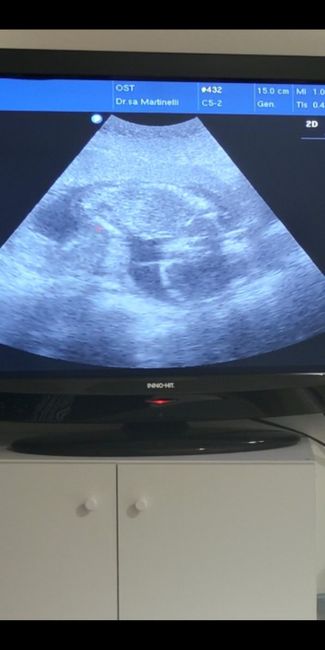

Future mamme luglio 2023 1

Eccolo il monello o la monella a testa in giù seduto sull utero